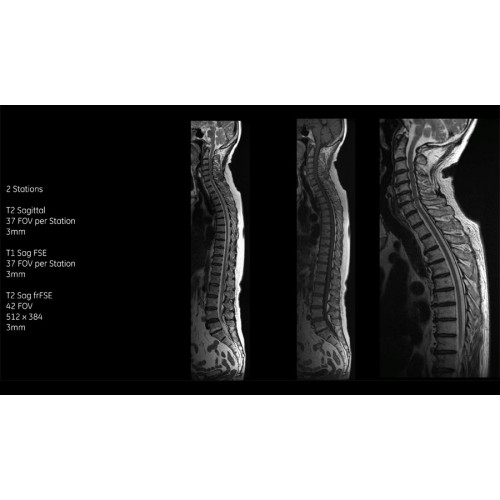

• Технология Digital Surround Technology (DST) — это новая технология объемной оцифровки данных, объединяющая сигналы от каждого элемента катушки. Прекрасное соотношение сигнал/шум и чувствительность поверхностных катушек в сочетании с превосходной однородностью и высокой проникающей способностью встроенной радиочастотной катушки — все это позволяет создавать качественные изображения не только позвоночника, но и всего тела.

Благодаря революционному программному пакету Silent Suite уровень шума снижается до 77 дБ, что всего на 3 дБ выше уровня окружающей среды. Программный пакет Silent Suite теперь включает полный пакет приложений для исследования ЦНС (T1, T2 FLAIR, DWI10, МРА). Кроме того, мы расширили возможности визуализации Silent за пределы ЦНС для исследований скелетно-мышечной системы и позвоночника. Silent Suite – платформа, содержащая в себе все импульсные последовательности для бесшумного сканирования.